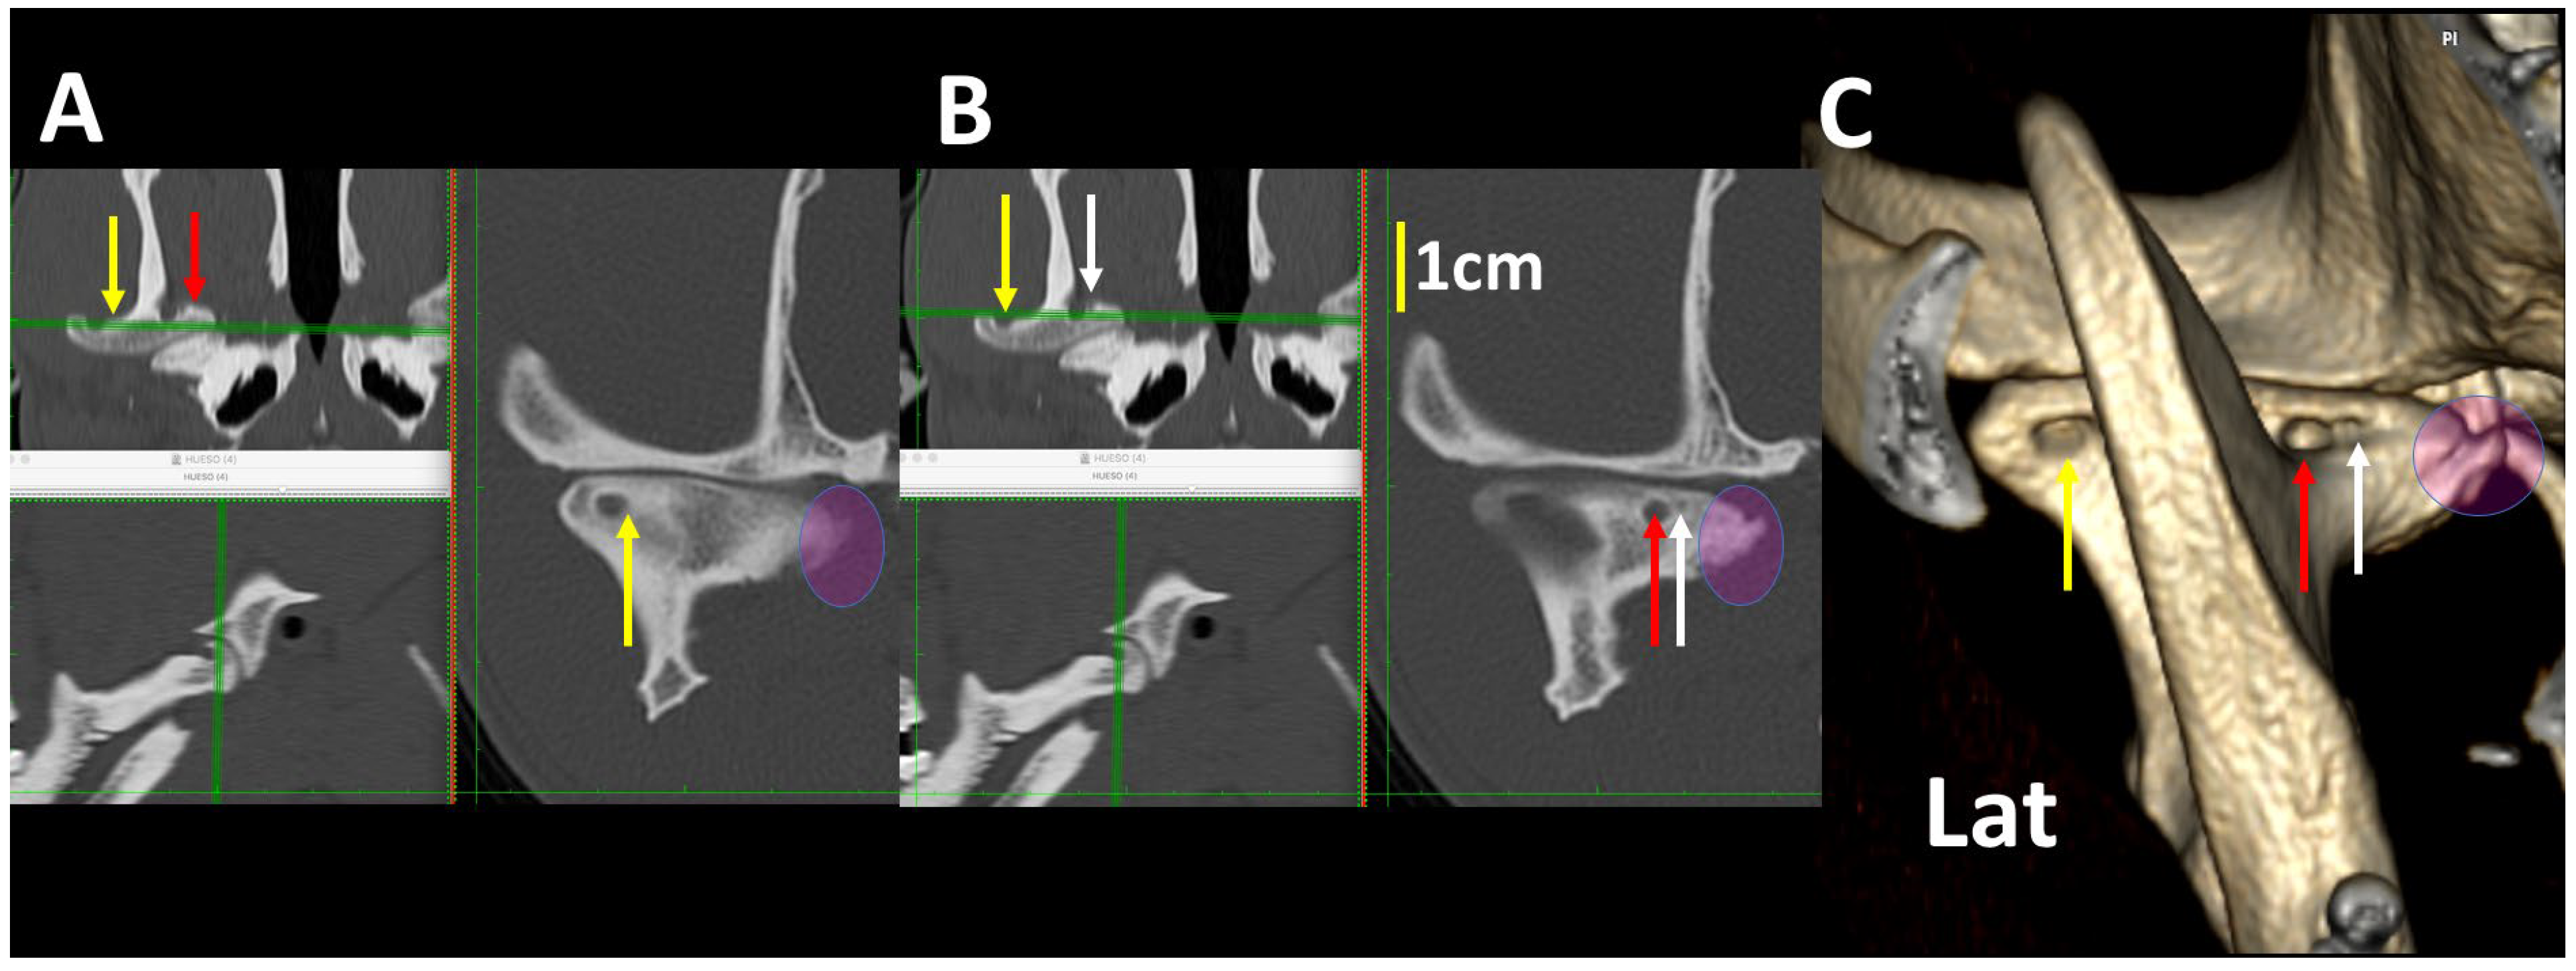

3.3. A Detailed Assessment of Each TMJ Comparing 3DVR Images with the Three Standard CT Planes

3.4. A Pictorial Essay of 3DVR Images in Some Pathological Cases